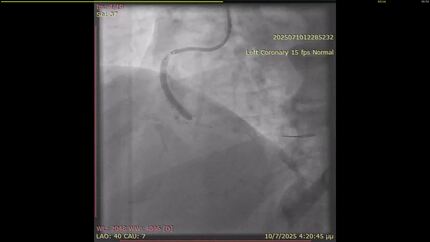

Percutaneous management of an intrapericardial paraganglioma using overlapping coronary covered stents